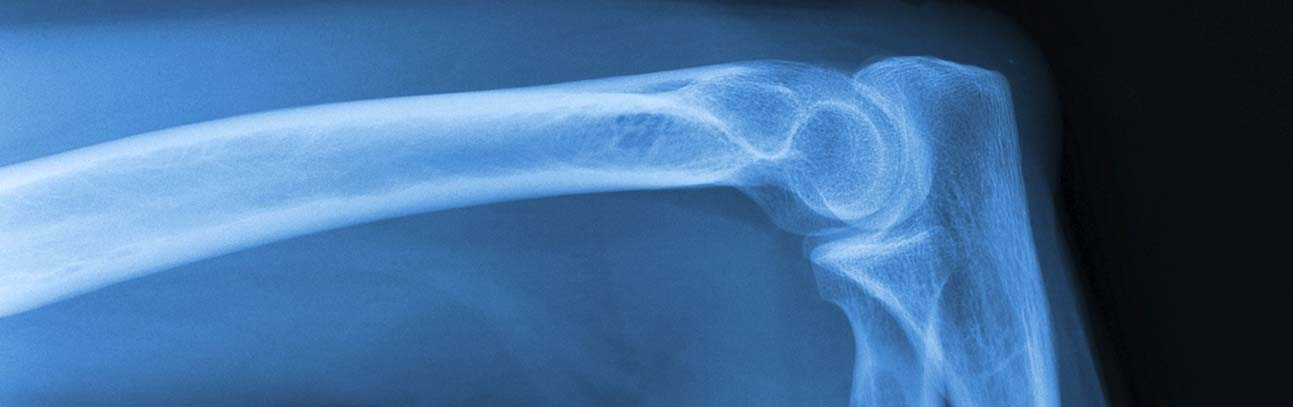

Before the Calaxo bone screw was recalled by the Food and Drug Administration (FDA) in November 2007, it was used in knee surgeries in the United States and overseas. The Calaxo screws were supposed to dissolve in the knee over time; however, in some cases, the bone screws dissolved early, which led to serious problems in some users.

The Calaxo® bone screw, also known as the “Calaxo Osteoconductive Interference Screw,” is a medical device that was implanted during surgery to help secure the anterior cruciate ligament (ACL) while it was being repaired.

The ACL is one of the four major ligaments in the knee and is the most commonly injured knee ligament. The ACL is usually torn by sudden twisting or stretching of the leg or by a sharp blow to the knee.